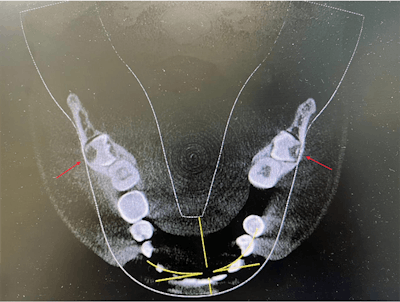

In the case report, the authors described how during the man's routine dental visit, bilateral impacted mandibular third molars were identified on a panoramic dental x-ray. The molars were transverse in the linguobuccal direction. A cone-beam computed tomography (CBCT) scan confirmed the molars were positioned in a linguobuccal direction on both sides, with thinning on the lingual cortical plates. No pathological findings were associated with the molars, the authors wrote.

Detailed evaluation of the CBCT results indicated the roots of the impacted teeth were not completely formed, and there was idiopathic osteosclerosis in the second premolar region, they wrote.